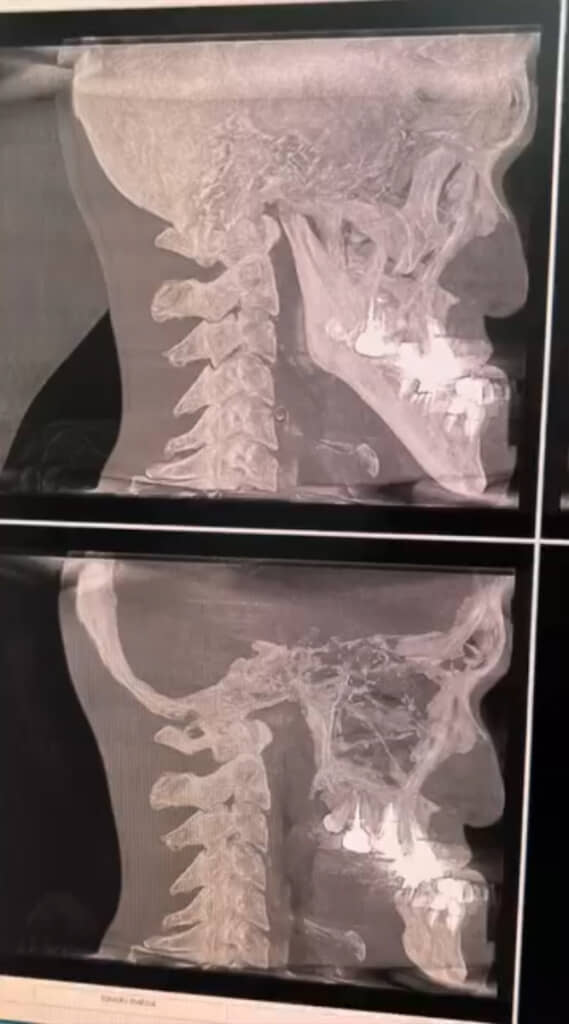

「世界一アゴの長いYouTuber」を自称する男性が、レントゲン撮影で自身の顎の骨を見て医師の診察を受けた結果が反響を呼んでいます。動画はInstagramで458万回以上再生され、“いいね”は2万件を突破しています(記事執筆時点)。

そしてレントゲン写真を見た城之内さんは、「すごい……」と自身の顎の長さに驚きの声をもらします。「こんな長いのって、あんまりないですもんね」と先生に聞いてみると、すぐに「ないです」との返答が。

また、いわゆるエラ(下顎角)のカドから下側を指し、「ここから先がめっちゃ長いですもんね」と城之内さん。すると先生から「角度も……」との言葉が続き、城之内さんの顎が唯一無二であることが分かる結果となっています。

城之内さん:驚きと共に謎の感動がありました。「こんなに育ってたんや……!」みたいな(笑)。ずっと一番近くにあるアゴなのに、骨で見ると前じゃなくて斜め下に出てることが分かったりと、新鮮でさらに愛着が沸きました(笑)。あと骨が鋭いの、武器みたいでカッコいいと思いました(笑)。